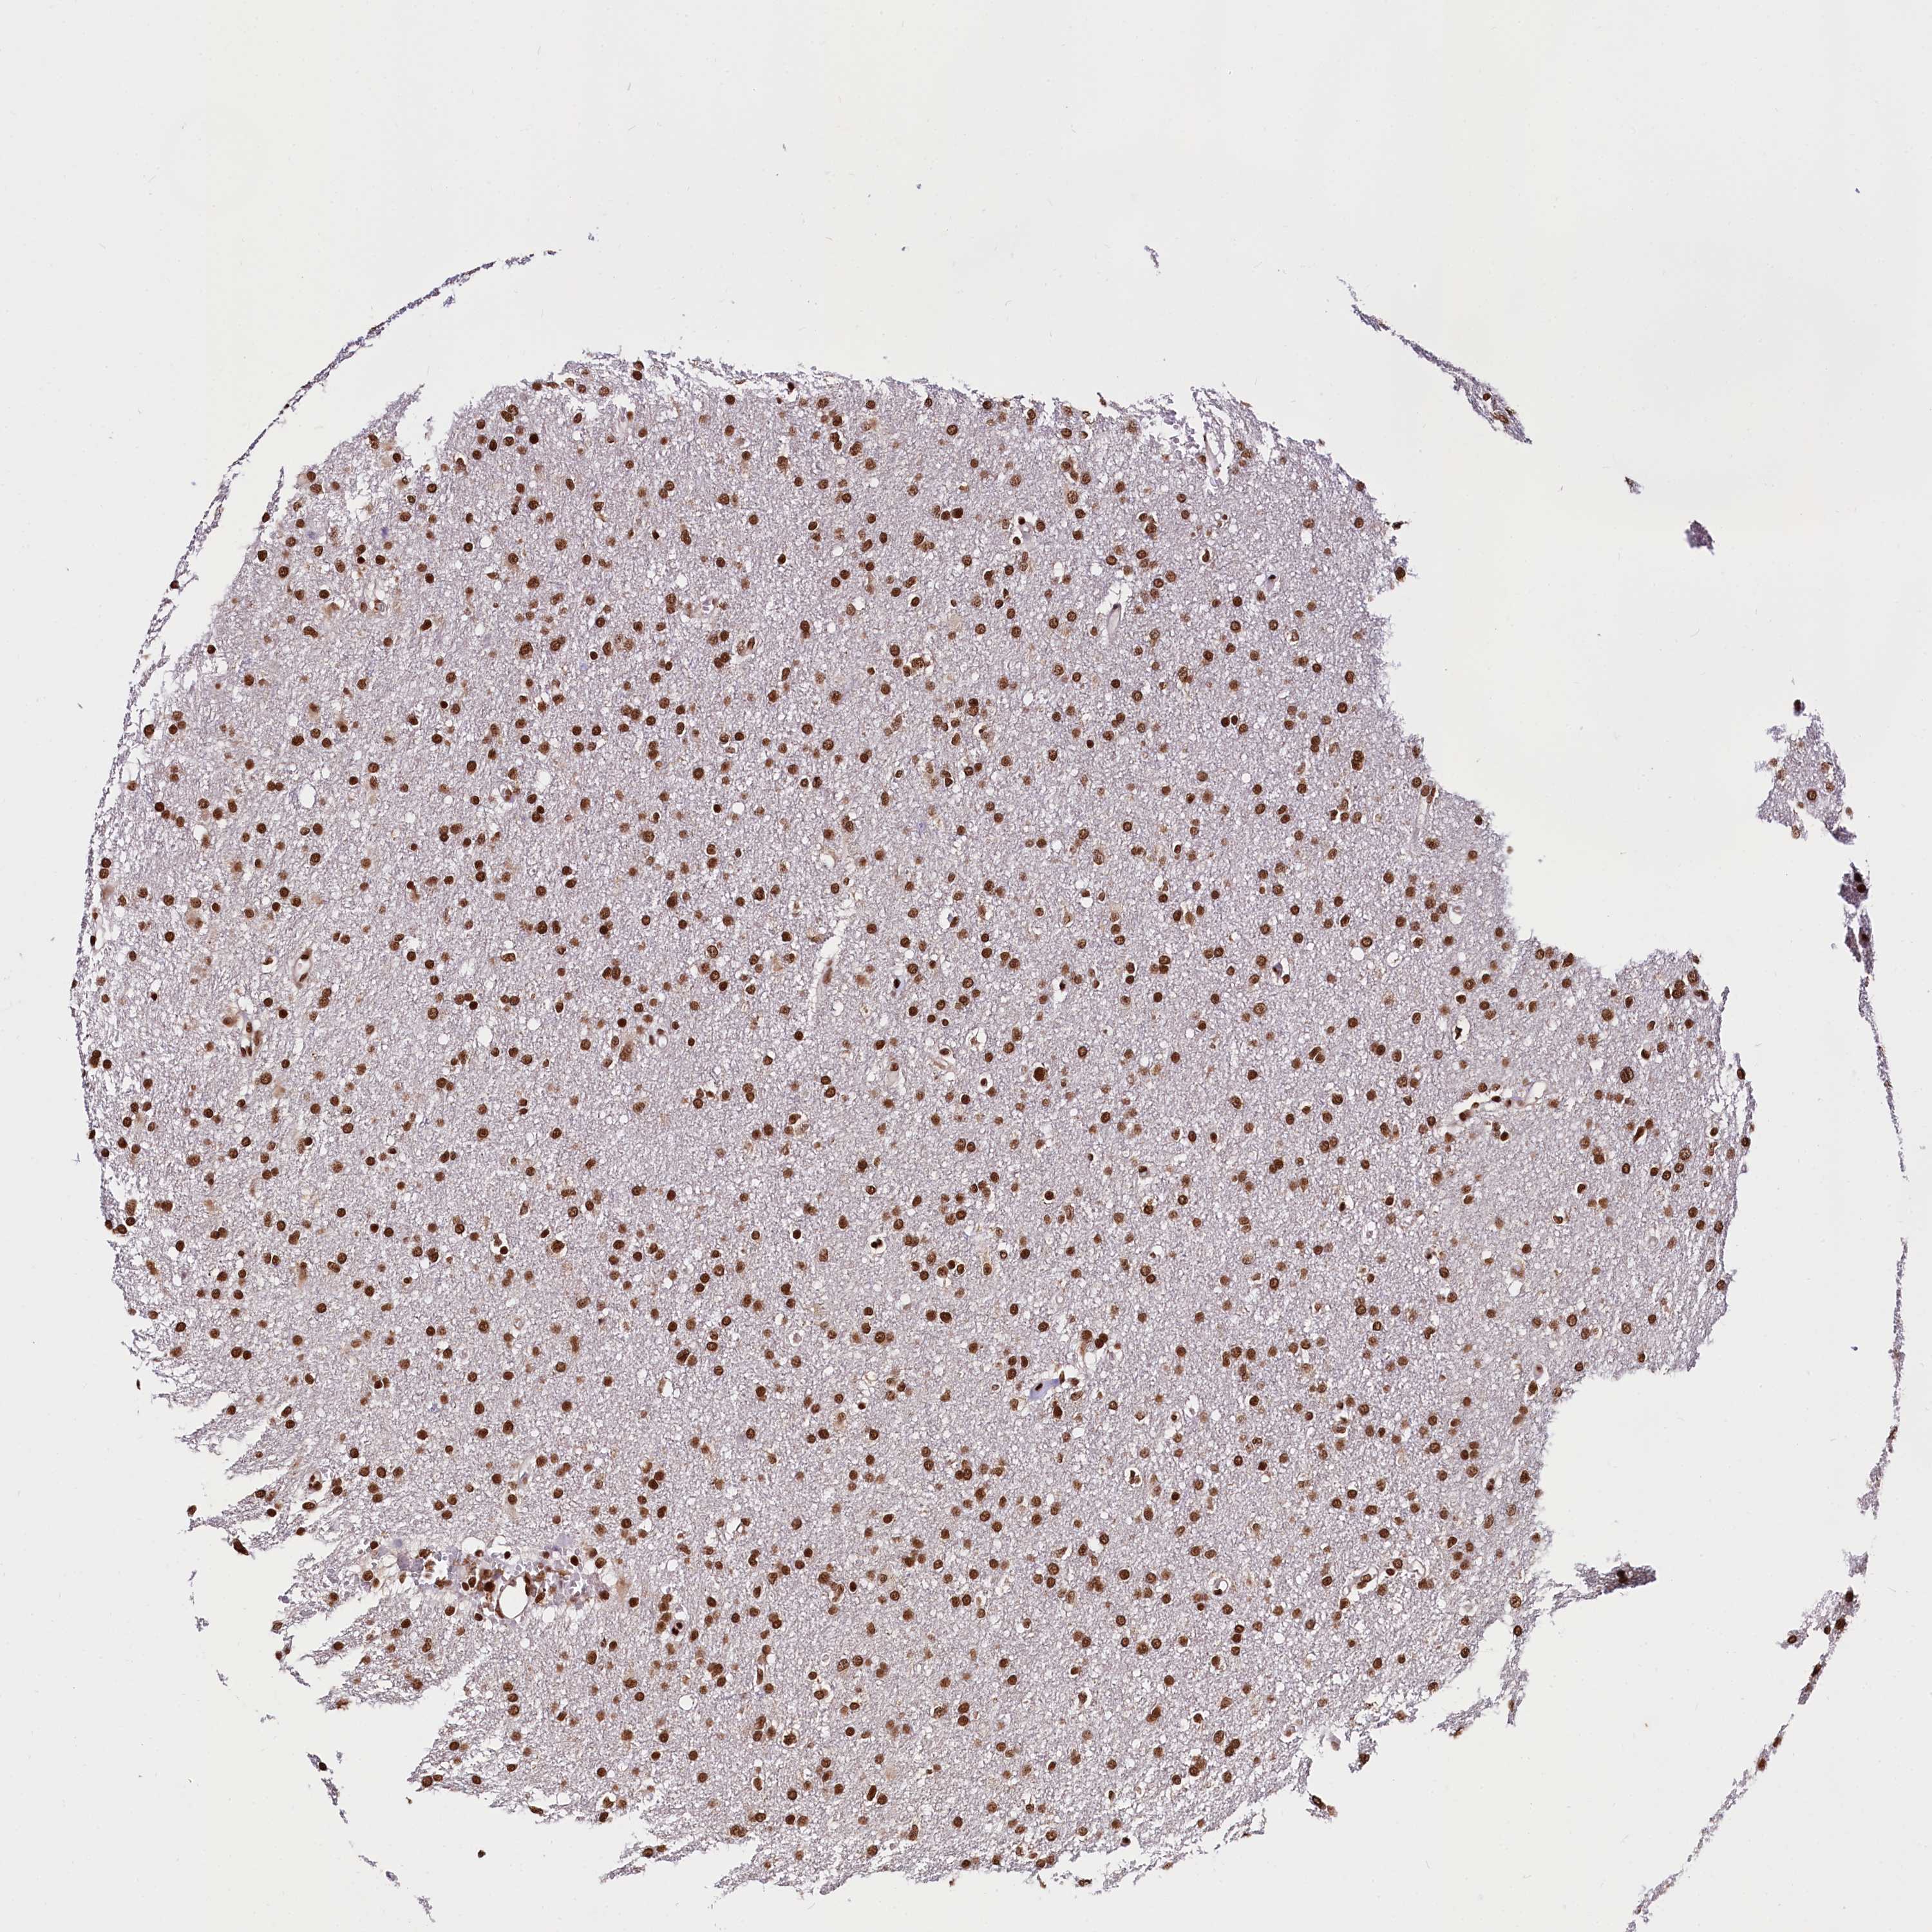

GLIOMA - Protein expressioni

A mouse-over function shows sample information and annotation data. Click on an image to view it in a full screen mode. Samples can be filtered based on level of antibody staining by selecting one or several of the following categories: high, medium, low and not detected. The assay and annotation is described here.

Note that samples used for immunohistochemistry by the Human Protein Atlas do not correspond to samples in the TCGA dataset.

Antibody stainingi

Antibody staining in the annotated cell types in the current human tissue is reported as not detected, low, medium, or high, based on conventional immunohistochemistry profiling in selected tissues. This score is based on the combination of the staining intensity and fraction of stained cells.

Each image is clickable and will lead to virtual microscopy that enables deeper exploration of all samples and also displays staining intensity scores, fraction scores and subcellular localization as well as patient and tissue information for each sample.

Antibody HPA039513

Antibody HPA040015

Staining

High

Medium

Low

Not detected

Intensity

Strong

Moderate

Weak

Negative

Quantity

>75%

75%-25%

<25%

None

Location

Nuclear

Cytoplasmic/membranous

Cytoplasmic/membranous,nuclear

Glioma, malignant, High grade

Glioma, malignant, Low grade